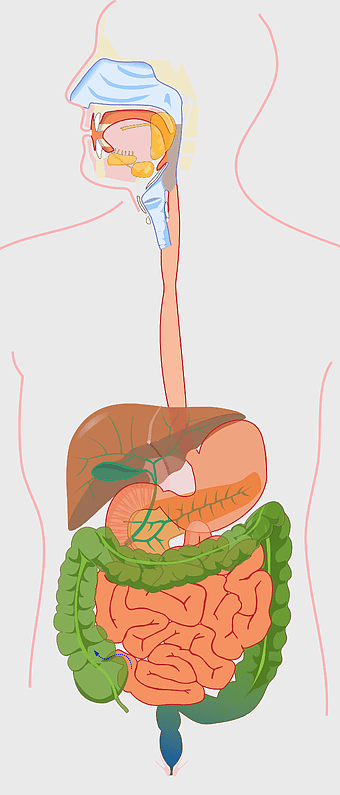

human digestive system, gastrointestinal tract anatomy, liver function, stomach and intestines, digestive health, internal organs diagram, human body systems -

509x768px

human gastrointestinal tract anatomy, human digestive system illustration, gastrointestinal disease symptoms, human body organ diagram, internal organ visualization, medical anatomy study, digestive health awareness -

1000x1000px

human digestive system illustration, gastrointestinal tract diagram, human body organ system, labeled digestive system, digestive anatomy chart, human internal organs, alimentary canal visualization -

771x900px

digestive system diagram, gastrointestinal tract chart, human anatomy illustration, small intestine function, digestive process visualization, internal organ layout, metabolic system overview -

600x800px